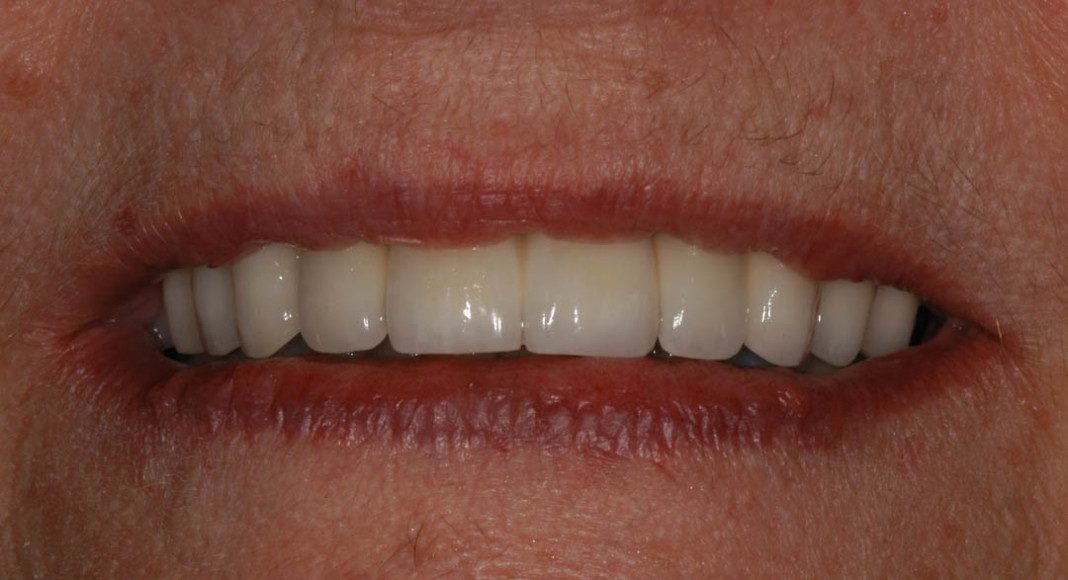

Case 1: This patient had a lot of old dental work and a few missing teeth. She had old crowns that were all different shades and several back teeth had gum recession significant enough that the roots were exposed and causing her sensitivity. She wanted a beautiful smile and teeth that weren’t sensitive to cold or sweets.

Final crowns and a bridge, lower arch. Her lower 8 front teeth were still in good shape, so we bleached them so she could choose a lighter shade with her final crowns and have a beautiful smile.